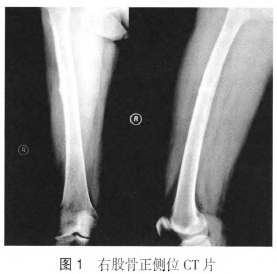

患者女,61岁,因“双侧大腿疼痛6个月,左侧外伤后疼痛加重伴活动受限ld”于2015年12月4日入院。6个月前,无明显诱因出现双侧大腿疼痛,不伴局部皮肤红肿热痛,未做特殊处理。1周前,疼痛稍有加重,X线片和CT可见双侧股骨外侧、中上段皮质增厚(图1)。MRI提示双侧股骨中上段髓腔内T1相低信号,T2相高信号,考虑股骨非典型骨折(不完全骨折),口服钙尔奇D(每日2次,1次1片)。1d前,行走时突然摔倒,左侧大腿疼痛剧烈,伴活动受限,急诊X线提示左侧股骨干骨折,断端明显移位。